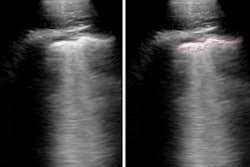

The researchers sought to evaluate the dynamics of chest CT opacity subtypes in COVID-19 before and after onset of symptoms. They utilized the Clara AI segmentation model (Nvidia) to automatically segment the total lung volume on serial chest CT exams in 29 mild COVID-19 patients from a single center in an outbreak zone.

After verifying the AI lung segmentation results, radiologists then manually segmented the lung opacities and noted the opacity subtypes. Next, the researchers employed generalized temporal curves to correlate the CT data with lab measurements such as blood cell count and procalcitonin levels. 3D visualizations were also used to reconstruct the evolution of COVID opacities.